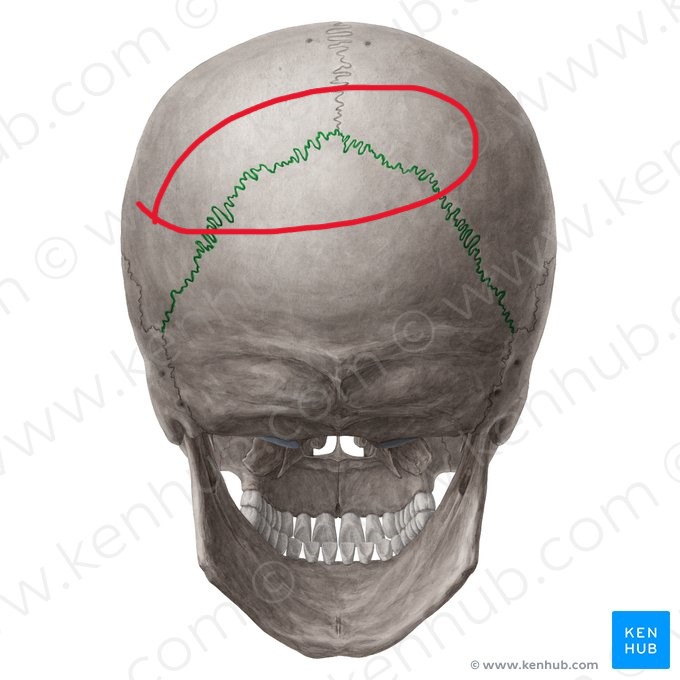

bregma

coronal suture (suture)

sagittal suture